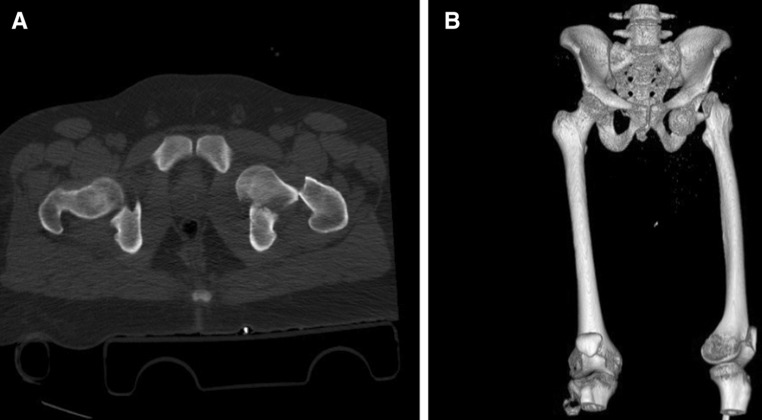

A CT scan for the hip was performed to locate the femoral head precisely and to exclude associated acetabular fractures (Fig. 2).

Fig. 2.

CT pelvis (a) with 3D reformat (b)